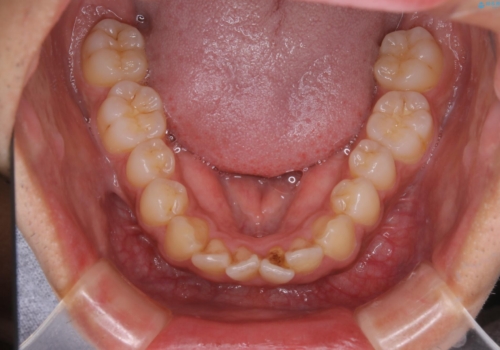

矯正をスタートする前にクリーニングを行いました。PMTC60分コースを行いました。

10年ぶりのクリーニングのため着色や歯石、プラークの量は多めでした。